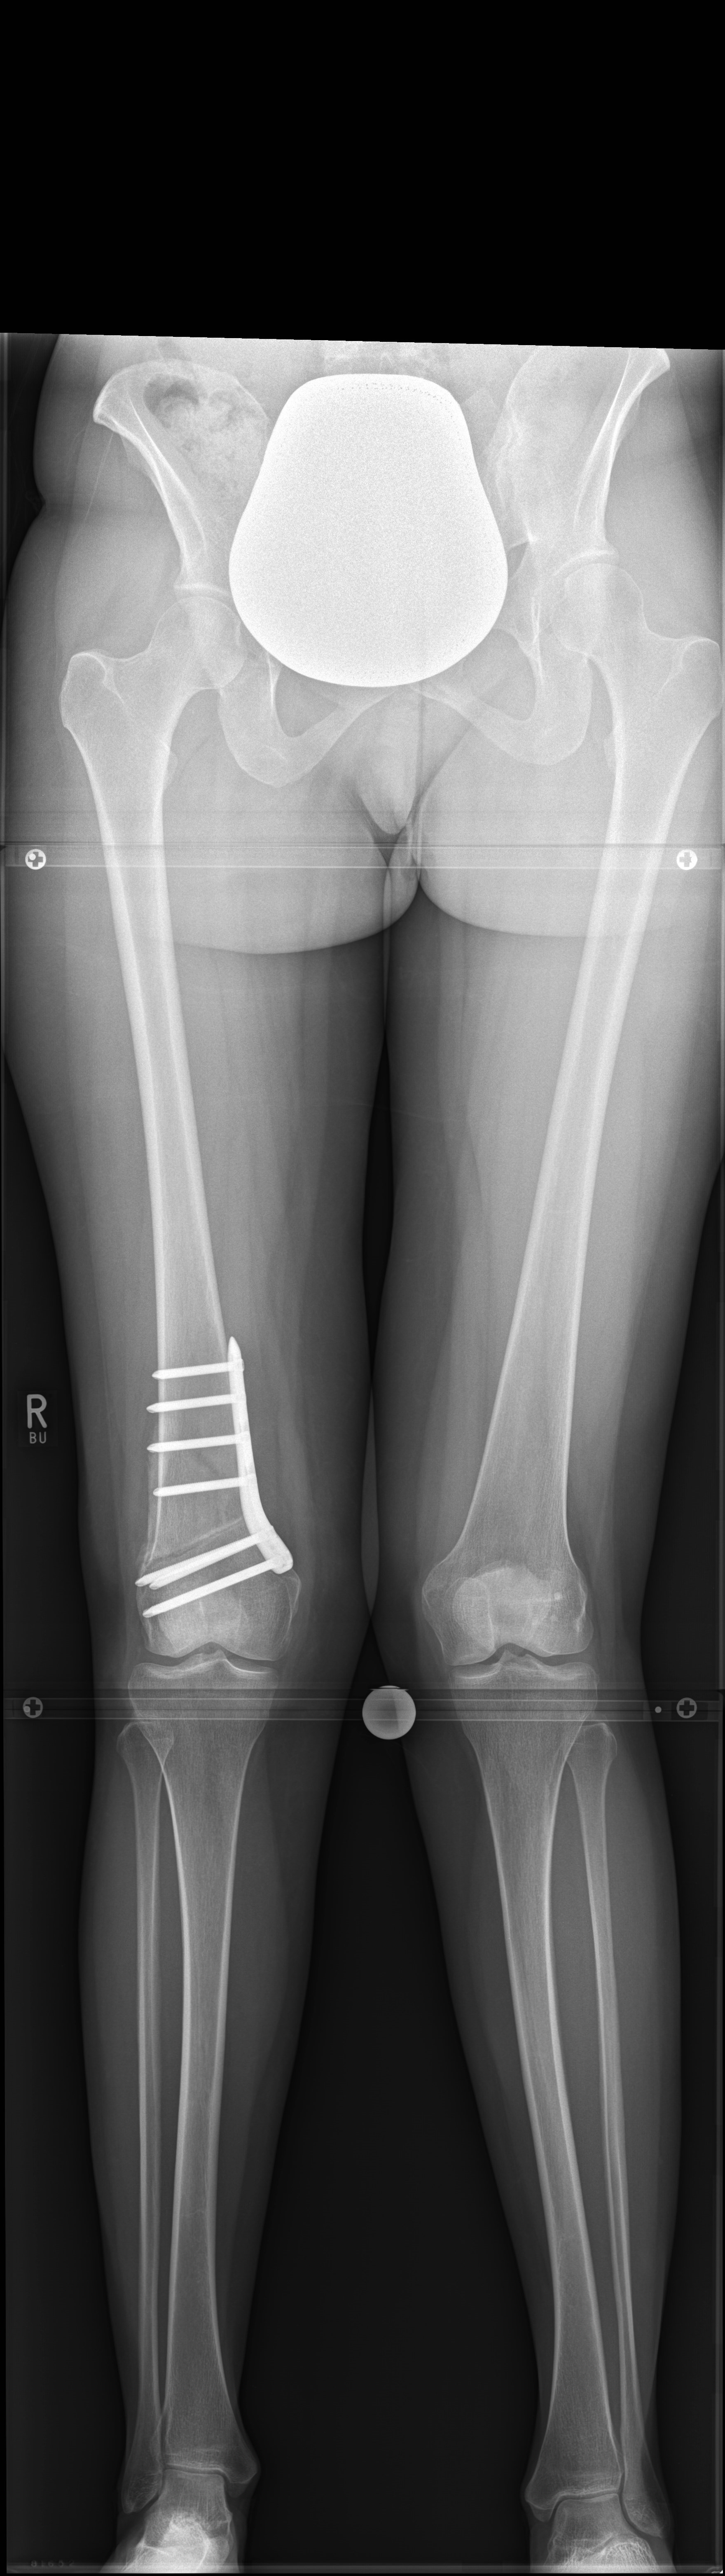

A 52-year-old man with a posttraumatic deformity 2 years after tibial plateau fracture AO/OTA 41C3.3e, PL, PM complained of pain after a normal working day. The patient was a heavy smoker. Activities like sports or hiking were discontinued. Surprisingly ligaments in the coronal and sagittal planes were stable. There was no effusion. Pain was localized in the medial compartment. The range of motion was limited to 0/0/130°. The deformity was corrected with a high tibial osteotomy.

Showcasing a high tibial osteotomy case